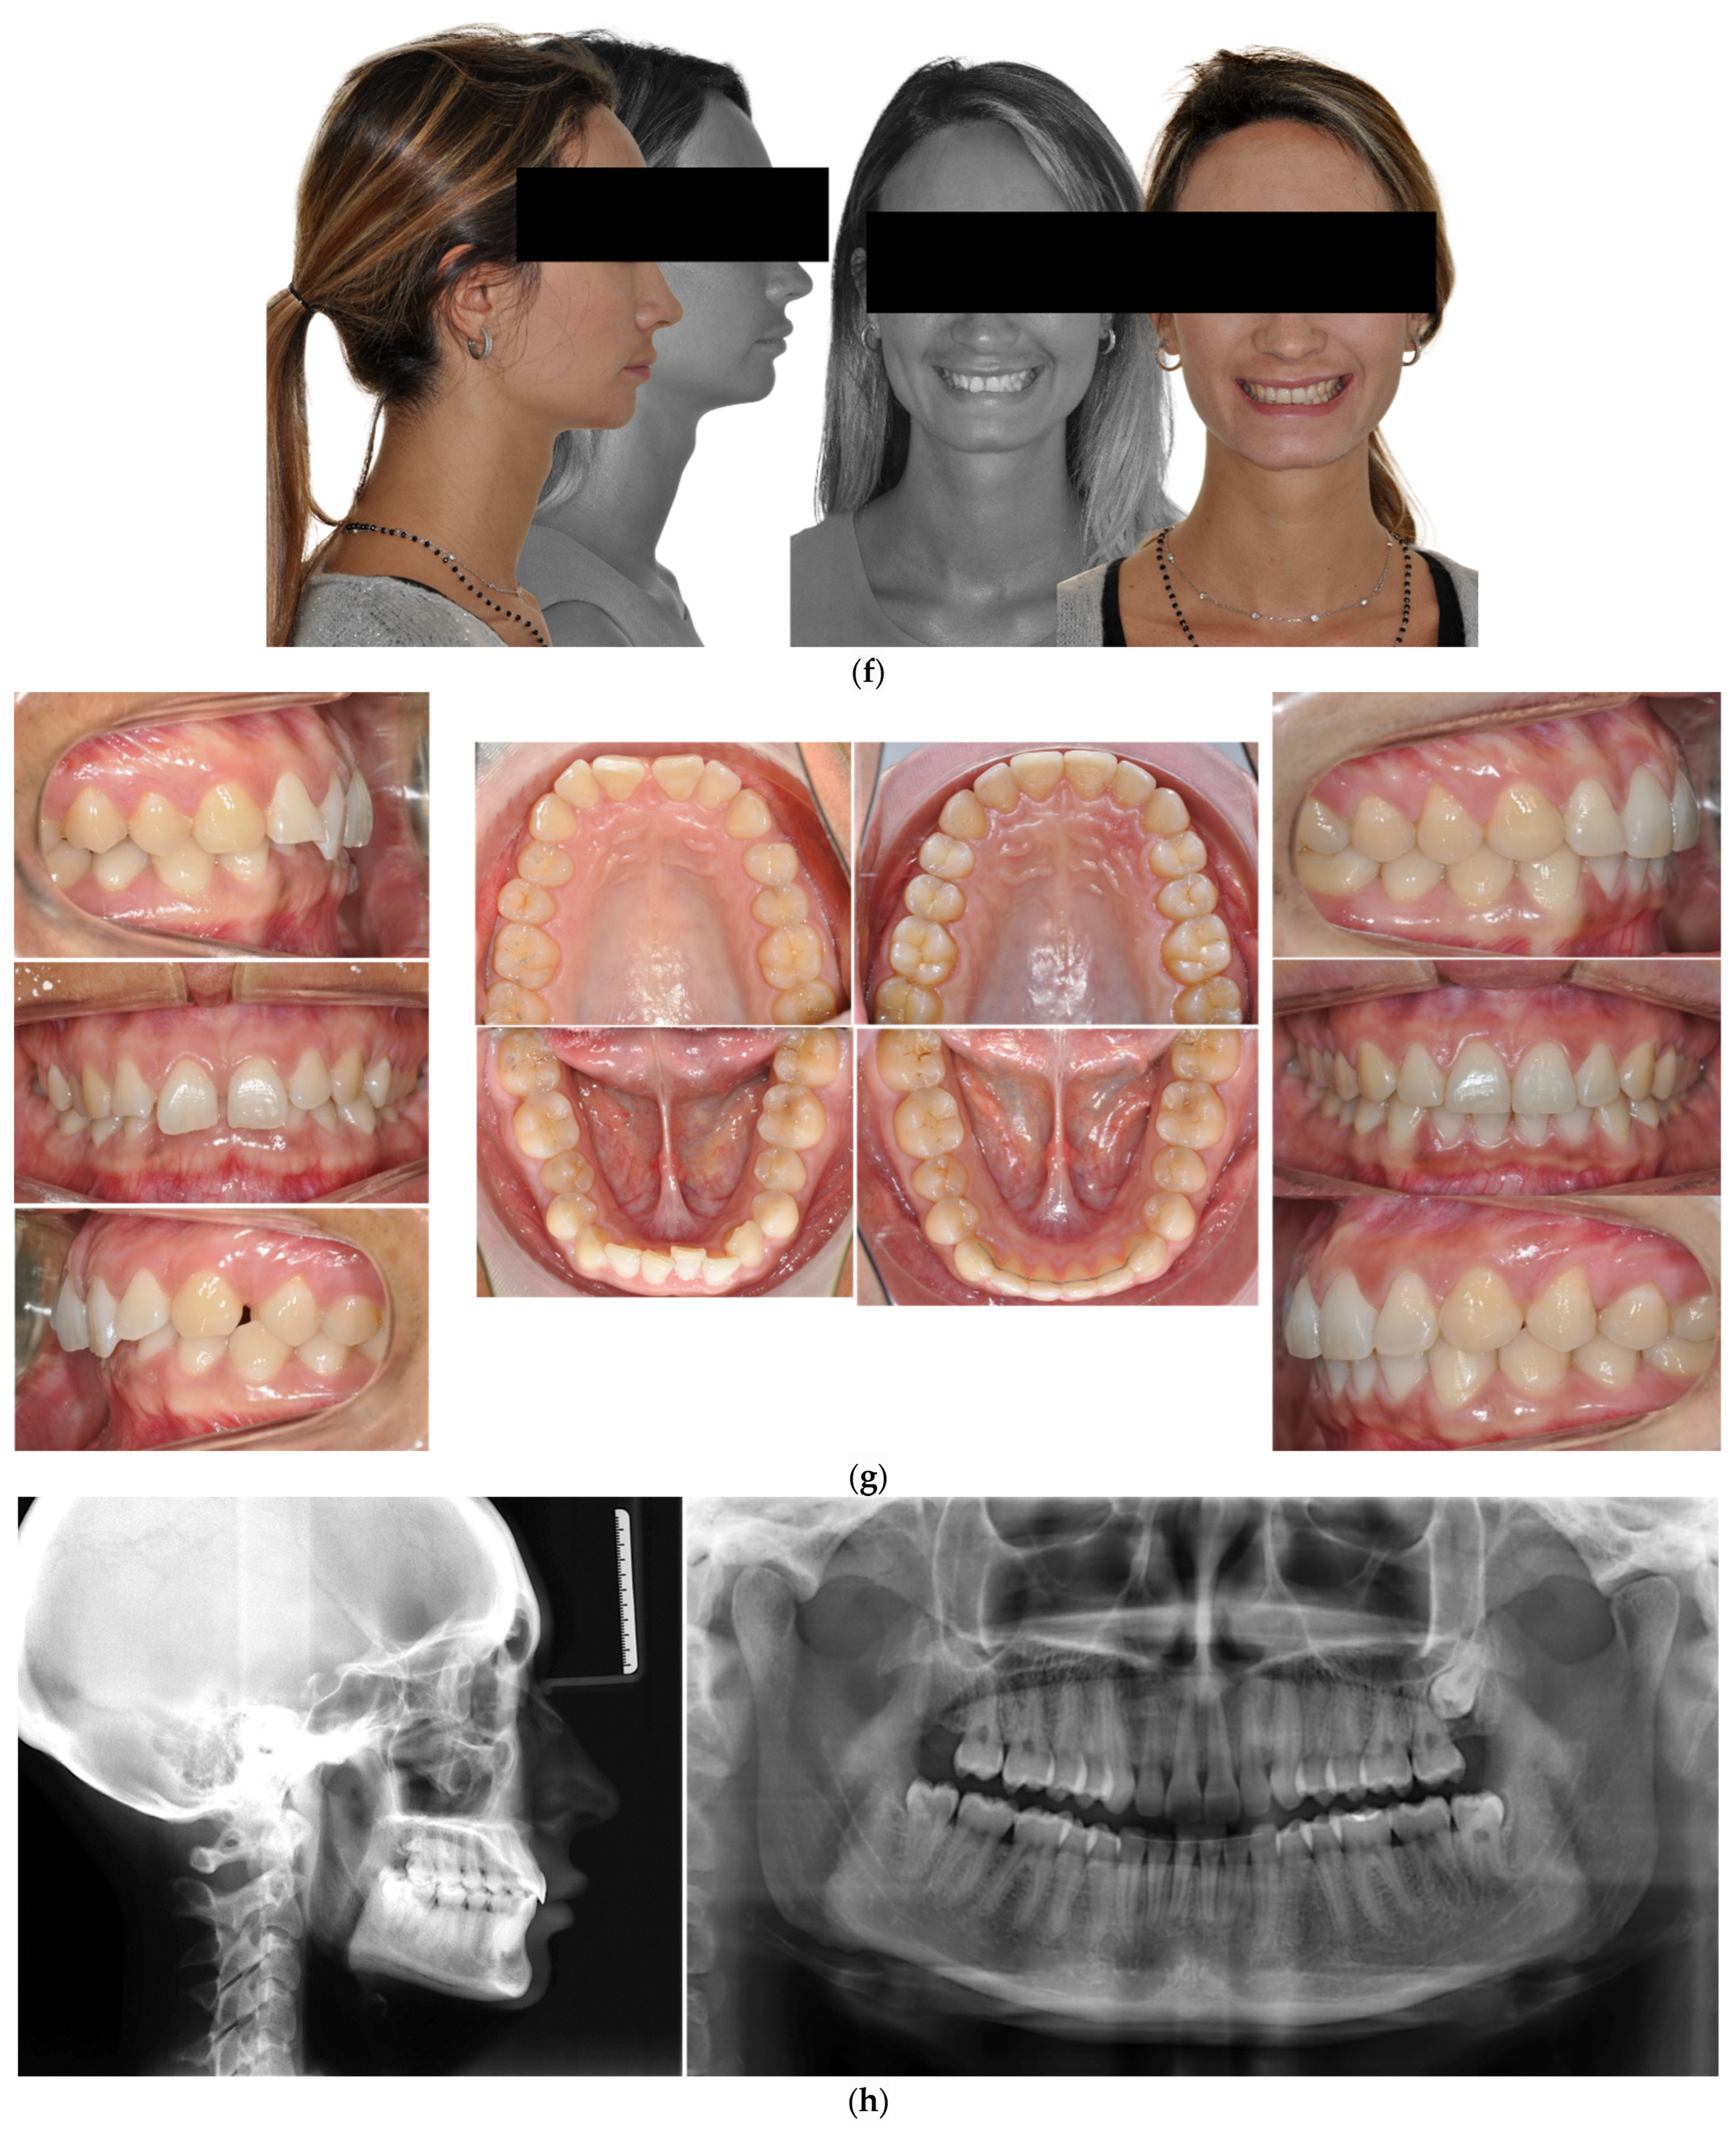

4.2. Case 2: Class III with a Deep Bite